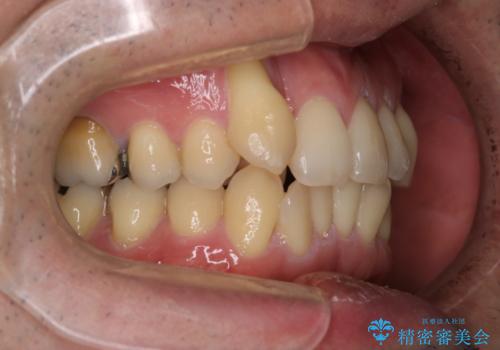

- 右上2番目の歯が舌側転位していることと前歯の叢生(がたつき)を主訴に来院されました。

右上の犬歯が初診時よりかなり歯根露出しており、矯正の力をかけるとさらに歯根露出するリスクがあるため、右上の2番目の歯を前に出すためにも

右上の犬歯を抜歯して歯並びを整える治療計画を立てました。